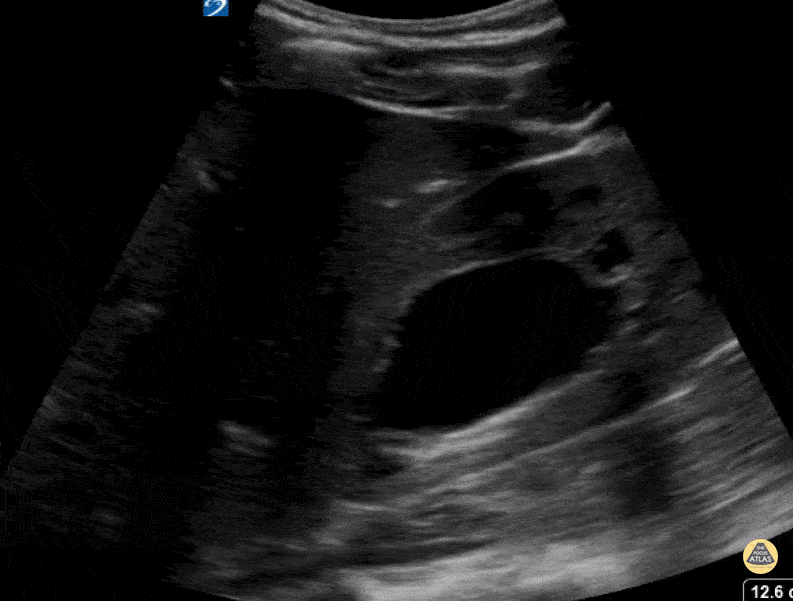

Genitourinary Jr